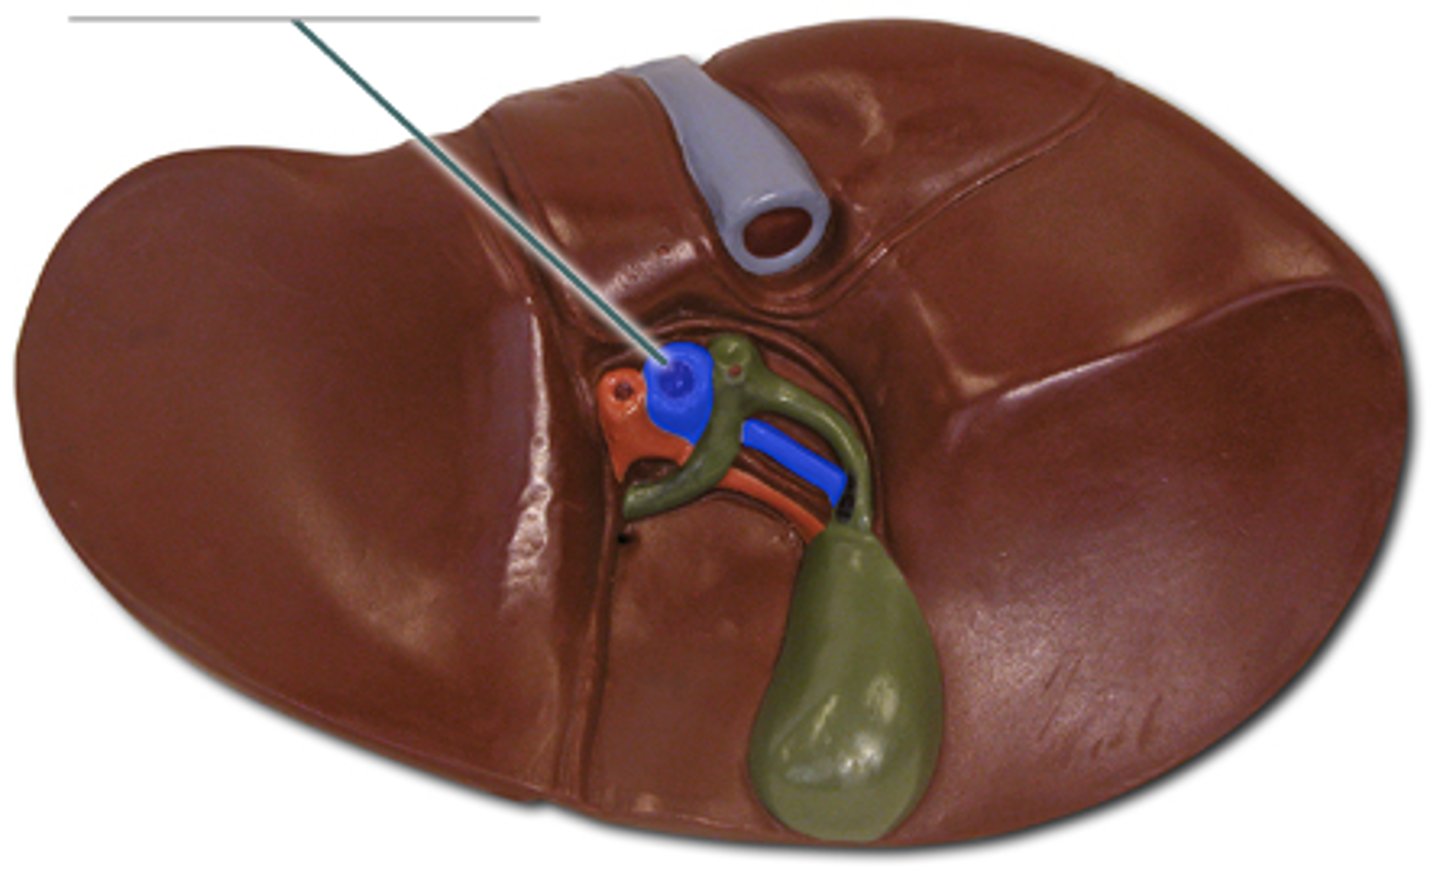

liver

pin

cystic duct

common hepatic duct

Gallbladder

portal vein

pancreatic duct

common bile duct

hepatopancreatic sphicter / duodenal papilla